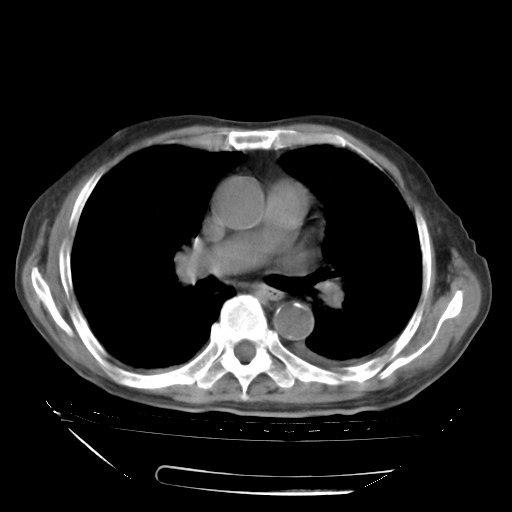

经过24天治疗,岳父的病情基本稳定。生活基本可以自理,可以下床活动。呼吸困难早已消失。体温基本正常。

只是甲强龙用80mg时血小板升到正常,改为60mg后又降到63×10*9/L。

主要治疗甲强龙80mg×14天,60mg×10天;同时抗结核(异烟肼+利福平+乙胺丁醇)。环磷酰胺0.1 tid 10天。

特别感谢胡教授、高管、桃子版主给出关键的治疗建议。桃版把所有肺部影像和全部临床资料请所在医院呼吸科、感染病科、结核科、临床免疫科专家会诊。临床免疫科专家制定了完整的治疗方案。

下一步治疗强地松+环磷酰胺+抗结核。 |